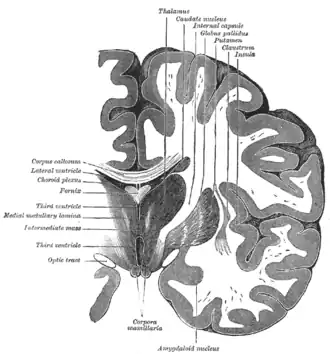

Coronale doorsnede van het brein (putamen is bovenaan gelabeld).

Het putamen en de nucleus caudatus vormen anatomisch gezien één structuur, het striatum dorsale, dat wordt doorkruist door de capsula interna. Daarnaast vormt het putamen samen met de globus pallidus de nucleus lentiformis. Het putamen is de buitenste structuur die behoort tot de basale kernen, een groep kernen met wijdverspreide verbindingen in de hersenschors, thalamus en hersenstam. Ook de substantia nigra, nucleus accumbens en de nucleus subthalamicus worden tot de basale kernen gerekend.

Het putamen komt in beide hersenhelften voor en is nauw verbonden met drie andere basale kernen. Ten eerste werkt het putamen samen met de nucleus caudatus om input vanuit de hersenschors te ontvangen. De twee structuren vormen zo de "ingang" tot de basale kernen. Ten tweede is het putamen verbonden met de globus pallidus, waaraan het output doorgeeft. Ten derde ontvangt de pars compacta substantiae nigrae input van het putamen.